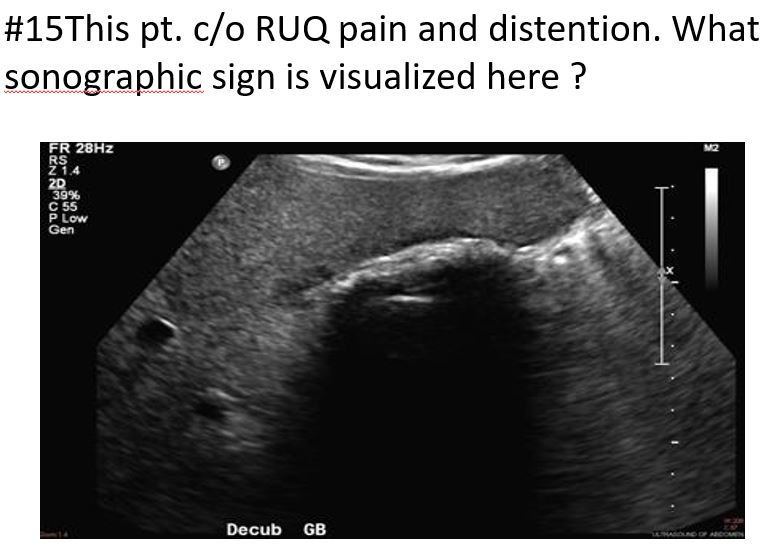

Distension (hydrops) of the gallbladder but showing what?

sludge with hydrops